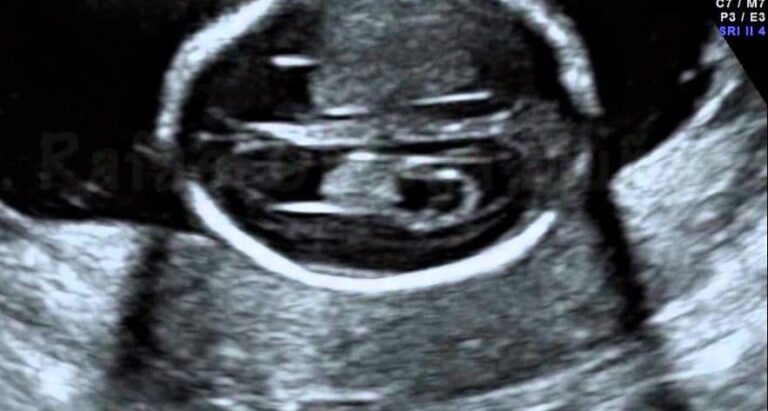

A Formação do Bebê Fotografada no Útero

Lennart Nilsson (nascido em 1922) é um fotógrafo e cientista sueco. Ele é famoso por suas fotografias in…